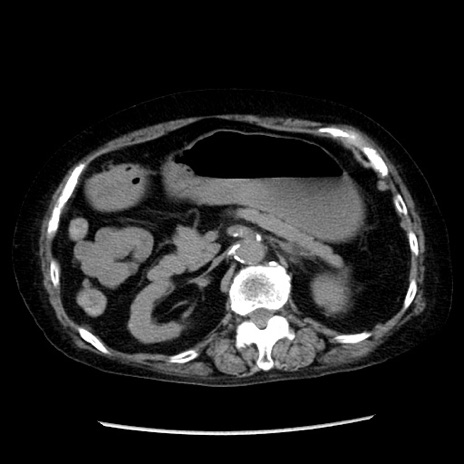

冠状断像

症例14(横断像)

【症例】 90歳代女性

【主訴】 腹痛・嘔吐

【現病歴】今朝から左側腹部痛を認めた。 経過観察していたが、嘔吐を認めたため来院。

【既往歴】 子宮癌術後

【身体所見】 意識清明、BP 127/54mmHg、P 98bpm Sp02 95%(RA)、BT 35.8°C、腹部平坦・軟腸ぜん動音聴取良好、右下腹部圧痛(+) 反跳痛なし

【データ】WBC 9800、CRP 0.46